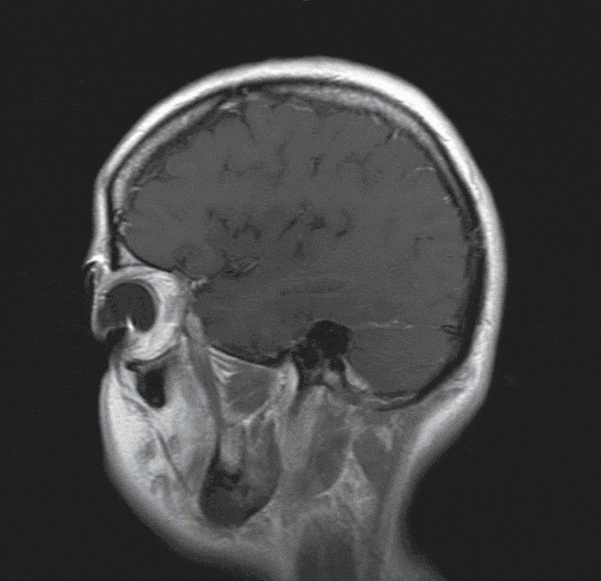

Neurinomas are usually benign tumors that arise on cranial nerves and are usually located at the base of the skull, for example, at the cerebellopontine angle. Among the most common neurinomas is vestibular schwannoma, which continues to be often referred to as acoustic neurinoma.